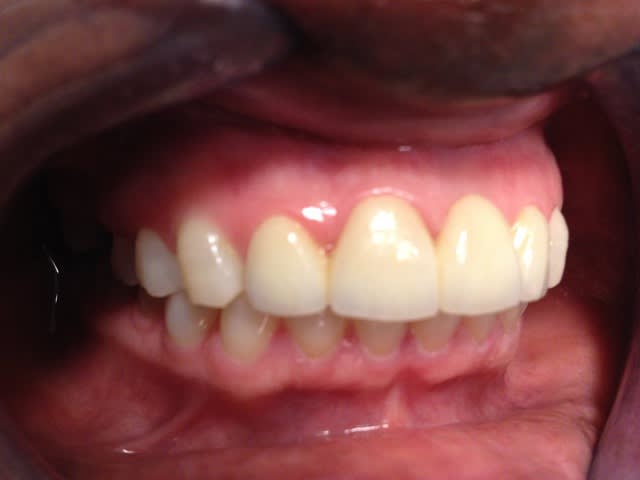

Je déterre mon poste en mettant les photos du cas. Désolé il manque le principal: la photo de l'état initial...

Donc par précaution, j'ai choisi de faire l'endo sur la 22, suite au coiffage direct (même si la dent était asymptotique pour la patiente).

Je n'ai pas osé faire que de l'Emax. J'ai décidé avec le labo de faire une armature Zircone avec de l'Emax pressée dessus.

Il y a les photos du biscuit, du bridge fini le jour de la pose et à 3 semaines.

A vos critiques, merci!

C'est très beau.

De ce que l'on peut en voir, c'est beau et propre.

je trouve le résultat très esthétique ;)